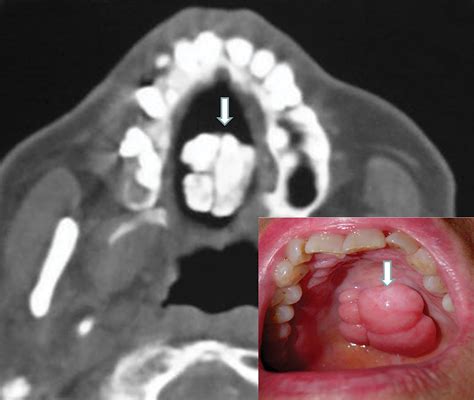

• Torus Palatinus: These occur on the roof of the mouth (hard palate), usually in the center. They can range from flat and wide to lobulated and prominent.

• Torus Mandibularis: These appear on the lingual (tongue-side) aspect of the lower jaw, usually above the mylohyoid line. These are often bilateral, meaning they appear on both the left and right sides of the lower jaw.